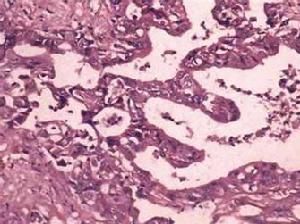

(1)肉眼形態學分類:根據腫瘤的大體形態可將膽管癌分為乳頭狀型、硬化型、結節型和瀰漫浸潤型4種類型。其中以浸潤型較多見,其次為結節型,而乳頭型較少見。膽管癌一般較少形成腫塊,而多為管壁浸潤、增厚、管腔閉塞;癌組織易向周圍組織浸潤,常侵犯神經和肝臟;病人常並發肝內和膽道感染而致死。

①乳頭狀癌:大體形態呈乳頭狀的灰白色或粉紅色易碎組織,常為管內多發病灶,向表面生長,形成大小不等的乳頭狀結構,排列整齊,癌細胞間可有正常組織。好發於下段膽管,易引起膽管的不完全阻塞。此型腫瘤主要沿膽管黏膜向上浸潤,一般不向膽管周圍組織、血管、神經淋巴間隙及肝組織浸潤。手術切除成功率高,預後良好。

②硬化型癌:表現為灰白色的環狀硬結,常沿膽管黏膜下層浸潤,使膽管壁增厚、大量纖維組織增生,並向管外浸潤形成纖維性硬塊;伴部分膽管完全閉塞,病變膽管伴潰瘍,慢性炎症,以及不典型增生存在。好發於肝門部膽管,是肝門部膽管癌中最常見的類型。硬化型癌細胞分化良好,常散在分布於大量的纖維結締組織中,容易與硬化性膽管炎、膽管壁慢性炎症所致的瘢痕化、纖維組織增生相混淆,有時甚至在手術中冷凍組織病理切片檢查亦難以作出正確診斷。硬化型癌有明顯的沿膽管壁向上浸潤、向膽管周圍組織和肝實質侵犯的傾向,故根治性手術切除時常需切除肝葉。儘管如此,手術切緣還經常殘留癌組織,達不到真正的根治性切除,預後較差。

③結節型癌:腫塊形成一個突向膽管遠方的結節,結節基底部和膽管壁相連續,其膽管內表面常不規則。瘤體一般較小,基底寬、表面不規則。此型腫瘤常沿膽管黏膜浸潤,向膽管周圍組織和血管浸潤程度較硬化型輕,手術切除率較高,預後較好。

④瀰漫浸潤型癌:較少見,約占膽管癌的7%。癌組織沿膽管壁廣泛浸潤肝內、外膽管,管壁增厚、管腔狹窄,管周結締組織明顯炎症反應,難以確定癌原始發生的膽管部位,一般無法手術切除,預後差。

(2)組織學分類:95%以上的膽管癌為腺癌,少數為鱗狀上皮癌、黏液癌,囊腺癌等,在原發性肝外膽管癌中,以膽總管癌最多見,33%~40%;其次為肝總管癌,30%~32%;肝總管分叉處,為20%;膽囊管4%。

肝外膽管癌組織學缺乏統一的分類,常用的是按癌細胞類型分化程度和生長方式分為6型:①乳頭狀腺癌;②高分化腺癌;③低分化腺癌;④未分化癌;⑤印戒細胞癌;⑥鱗狀細胞癌等,以腺癌多見。分型研究報告各家不盡一致,但最常見的組織學類型仍為乳頭狀腺癌、高分化腺癌,占90%以上,少數為低分化腺癌與黏液腺癌,也有罕見的膽總管平滑肌肉瘤的報告等。